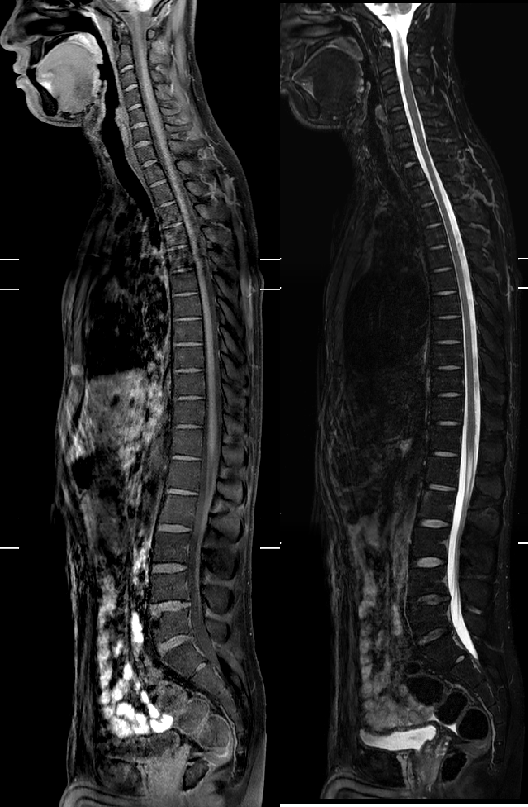

骨关节及脊柱方向

相对传统核磁,3.0T核磁可以做到全脊柱成像,对于全脊柱多发病变一目了然;在高分辨率扫描基础上,骨质结构及关节软骨、滑膜显示更加清晰,有利于骨关节疾病诊断。

全脊柱成像